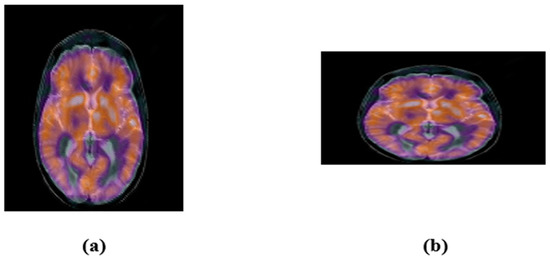

- Johnson, K.A.; Becker, J.A. The Whole Brain Atlas. Available online: http://www.med.harvard.edu/AANLIB/home.html (accessed on 19 April 2022).